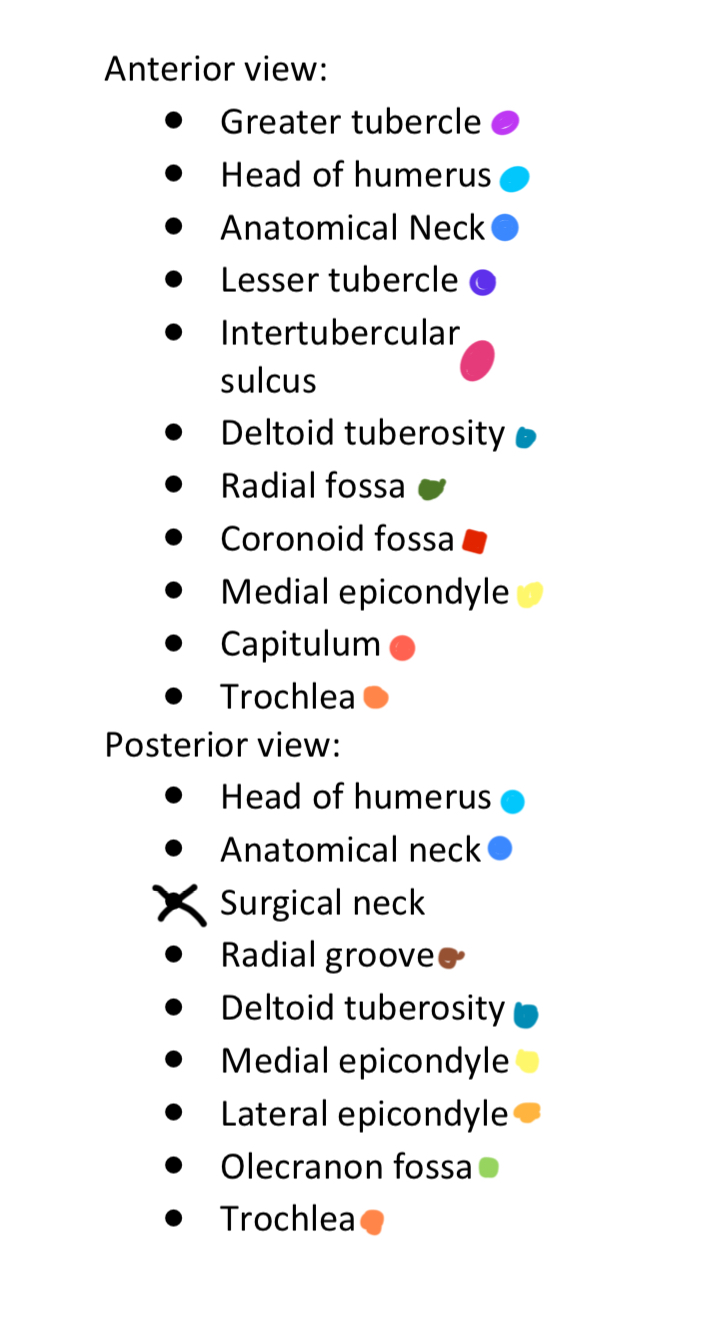

Anterior & Posterior Views of the Humerus

Light Purple

Greater Tubercle

2

New cards

Light Blue

Head of Humerus

3

New cards

Dark Blue

Anatomical Neck

4

New cards

Dark Purple

Lesser Tubercle

5

New cards

Pink

Intertubercular Sulcus

6

New cards

Cyan

Deltoid Tuberosity

7

New cards

Dark Green

Radial Fossa

8

New cards

Red

Coronoid Fossa

9

New cards

Yellow

Medial Epicondyle

10

New cards

Salmon

Capitulum

11

New cards

Dark Orange

Torchlea

12

New cards

Brown

Radial Groove

13

New cards

Light Orange

Lateral Epicondyle

14

New cards

Light Green

Olecranon Fossa